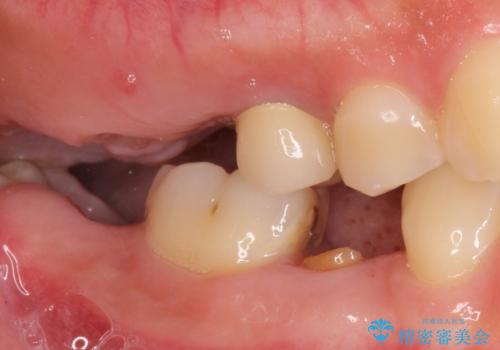

![[ 途中からの治療 ] 他院で行った根管治療後のセラミック治療の症例 治療前](https://seimitsushinbi.jp/wp/wp-content/uploads/2021/08/ec112886b077b95f063460404571fcd5-500x350.jpg?v=1629978236)

![[ 歯牙破折 ] 違和感のある大臼歯 ブリッジ治療の症例 治療前](https://seimitsushinbi.jp/wp/wp-content/uploads/2021/08/IMG_9577-500x350.jpg?v=1629711075)